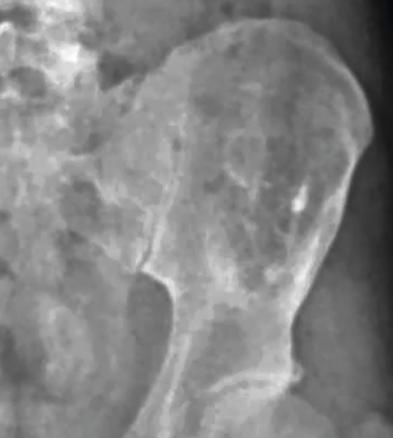

Arnaud, 37 ans, militaire sportif et asymptomatique, consulte avec les radiographies prescrites pour une expertise médicale initiale au parachutisme. L’aile iliaque gauche est le siège d’une lacune osseuse assez importante de découverte fortuite (fig. 1 ).

Un complément d’imagerie par TDM (fig. 2 ) confirme l’existence d’une lésion soufflante mixte (graisse et os) non vascularisée à caractère très probablement bénin, évoquant soit un kyste osseux solitaire vieilli, soit une dysplasie fibreuse, de localisation tout à fait singulière.